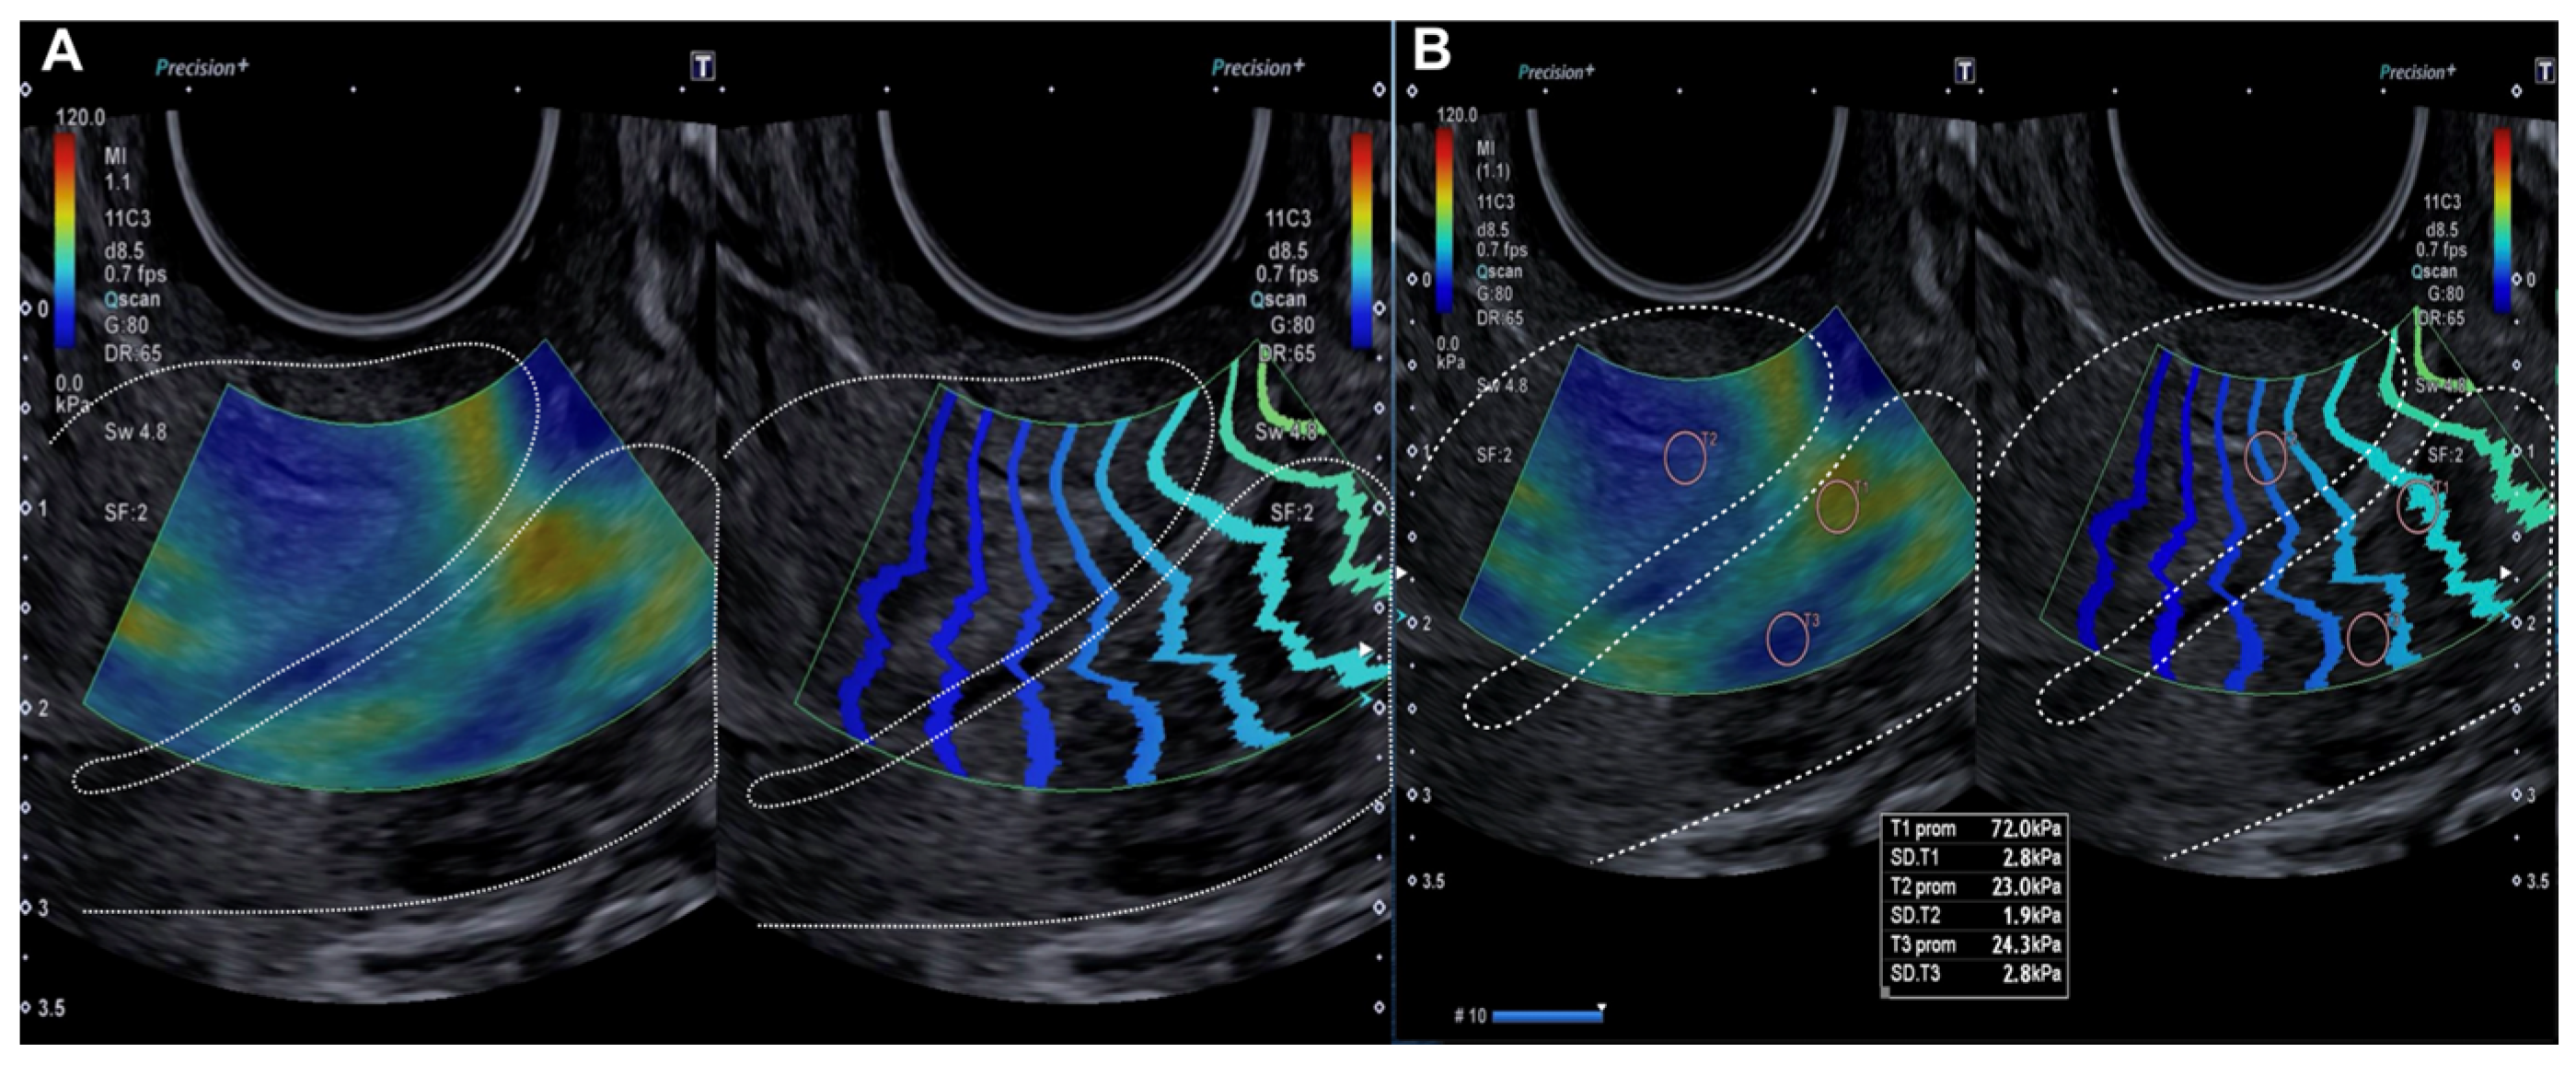

2.2.2. Evaluation Using SonoElastoColposcopy

| Exocervix (kPa) | 19.98 (±9.29) | 105.42 (±36.32) | p < 0.0001 |

| Endocervix (kPa) | 18.5 (±9.07) | 109.8 (±40.86) | p < 0.0001 |

| Without lesion (n = 6) | 1/6 (16.67%) | 0.456 (p < 0.05) | 5/6 (83.33%) | 0.815 (p < 0.05) |

| Upper left quadrant (n = 16) | 13/16 (81.25%) | 15/16 (93.75%) | ||

| Lower left quadrant (n = 3) | 3/3 (100%) | 2/3 (66.67%) | ||

| Lower right quadrant (n = 26) | 8/26 (30.77%) | 18/26 (69.23%) | ||

| Upper right quadrant (n = 13) | 7/13 (53.85%) | 12/13 (92.31%) | ||

| Various quadrants (n = 18) | 14/18 (77.78%) | 18/18 (100%) | ||

| All (n = 82) | 46/82 (56.10%) | 70/82 (85.37%) | ||